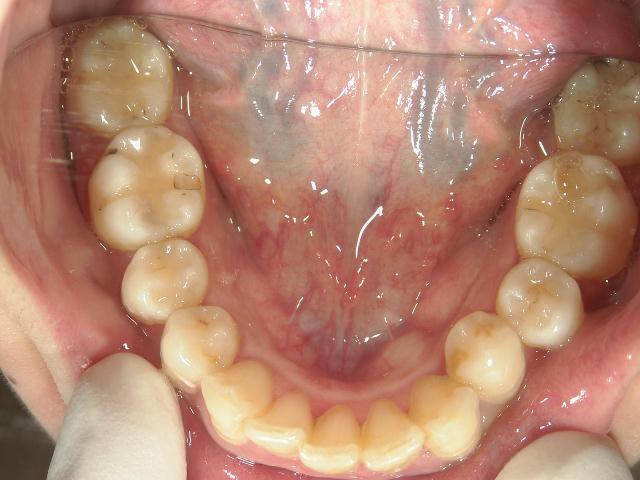

矯正歯科 治療前 上顎

矯正歯科 治療前 下顎